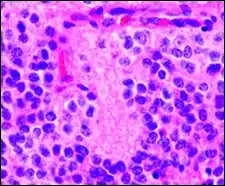

Structure of a Homer Wright pseudorosette

Perivascular pseudorosette

A perivascular pseudorosette consists of a spoke-wheel arrangement of cells with tapered cellular processes radiates around a wall of a centrally placed vessel. The modifier “pseudo” differentiates this pattern from the Homer Wright and Flexner-Wintersteiner rosettes, perhaps because the central structure is not actually formed by the tumor itself, but instead represents a native, non-neoplastic element. Also, some early investigators argued about the definition of a central lumen, choosing “pseudo” to indicate that the hub was not a true lumen but contained structures. Nevertheless, this pattern remains extremely diagnostically useful and the modifier unnecessarily leads to confusion. Perivascular pseudorosettes are encountered in most ependymomas regardless of grade or variant. As such, they are significantly more sensitive for the diagnosis of ependymomas than true ependymal rosettes. Unfortunately, perivascular pseudorosettes are also less specific in that they are also encountered in medulloblastomas, PNETs, central neurocytomas, and less often in glioblastomas, and a rare pediatric tumor, monomorphous pilomyxoid astrocytomas.[2]

Micrograph of perivascular pseudorosettes